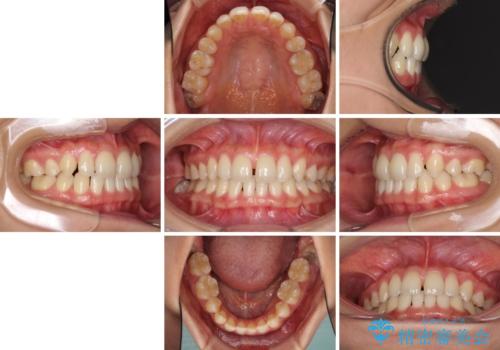

- 以前の矯正治療の後戻りにより、上の前歯にスペースができたことを気にして来院された患者様です。

インビザラインを用いて前歯のスペースを閉じつつ、上下の咬み合わせを構築していくこととしました。

隙間の空いてしまった前歯は、矯正治療で治療を行っても後戻りが起こりやすい傾向にあります。

マウスピースの保定装置をしっかりと装着しても空いてしまうため、細いワイヤーによる保定を併用することで後戻りを防止しています。